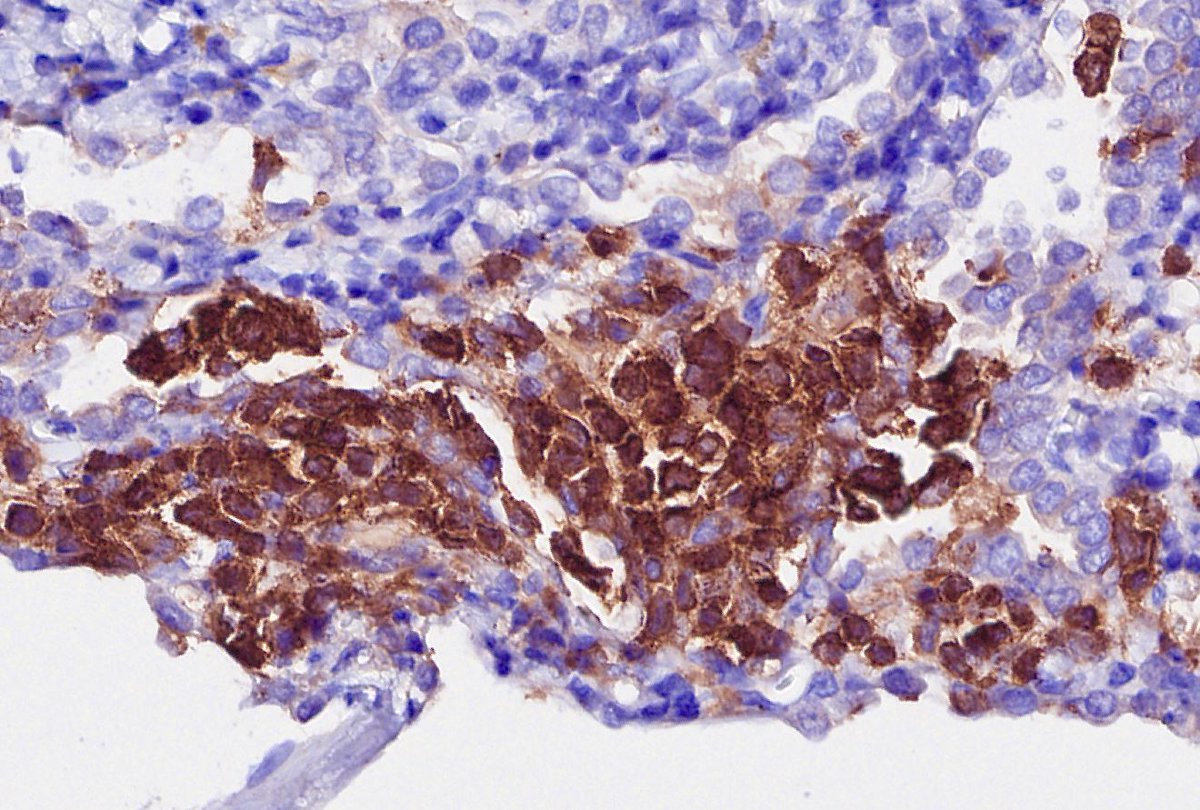

Explants from woman in her mid 40s. Clinical history on req: pulmonary hypertension. IHC is CD1a. Unifying diagnosis?

Thanks to all who engaged! Although uncommon, chronic LCH can lead to severe secondary pulmonary HTN which is what we see here. A spectrum of arterial lesions, including plexiform, dilatation, and medial hypertrophy. Wishing the patient a new lease on life with new lungs!